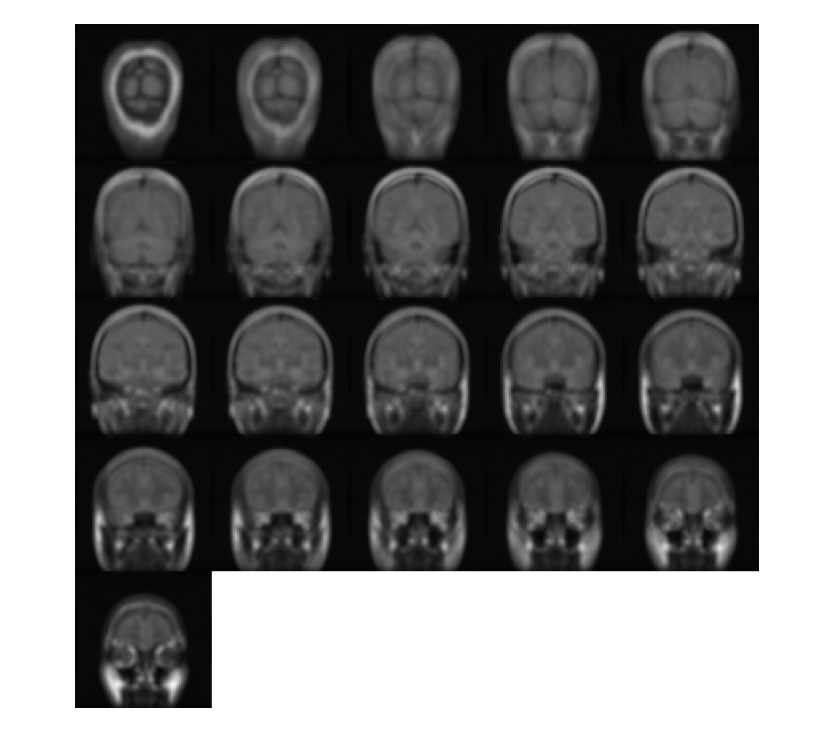

Загрузите 3-D полутоновый объем MRI. Отобразите плоскости объема.

load mristack;

montage(mristack,'BackgroundColor','w')

Figure contains an axes object. The axes object contains an object of type image.

Создайте 3-D эллипсоидальный фильтр. Задайте длину полуоси 7 пикселей в y (строки) и x (столбцы) направления и длина полуоси 3 пикселей в z (плоскости) направление.

H = fspecial3('ellipsoid',[7 7 3]);

Сглаживайте объем с фильтром.

volSmooth = imfilter(mristack,H,'replicate');

Отобразите плоскости сглаживавшего объема.

montage(volSmooth,'BackgroundColor','w')